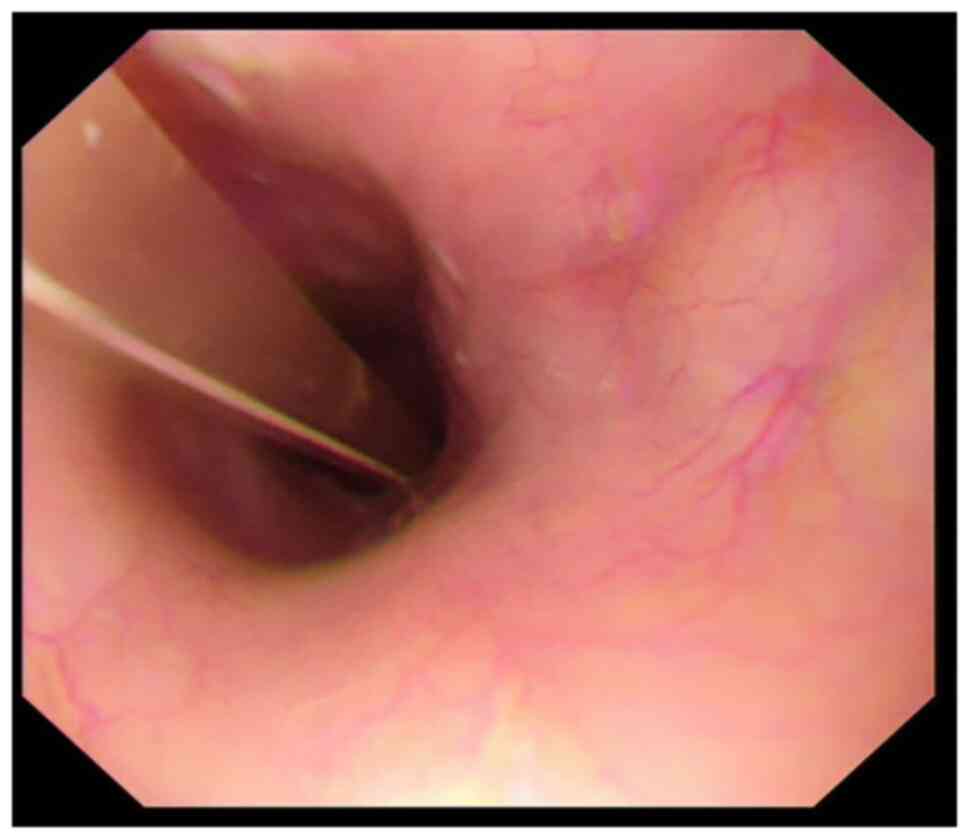

Fusion of the anaplastic lymphoma kinase (ALK) gene is a rare driver in non‑small cell lung cancer (NSCLC). Lorlatinib is a third‑generation ALK inhibitor approved for the treatment of locally advanced or metastatic ALK+ NSCLC. The traditional administration method of lorlatinib is whole tablet ingestion, while the efficacy effect of gastric tube injection after water dissolution remains unclear. In the present report, a marked response to lorlatinib in a 49‑year‑old patient with ALK+ NSCLC who was administered lorlatinib through a gastric tube, was described. The patient had received chemotherapy combined with immune checkpoint inhibitors prior to targeted drug therapy and developed hyperprogression, which was mainly manifested as rapid enlargement of the primary lesion with multiple new systemic metastases, accompanied by poor performance status score, esophageal compression and difficulty eating. The patient was injected with pre‑dissolved lorlatinib through the nasogastric tube. After 6 days, related symptoms, such as dyspnea and dysphagia, were relieved. After 18 days, the esophageal stenosis was significantly alleviated, and the gastric tube was removed. In conclusion, gastric tube injection be used as a means of lorlatinib administration in patients with ALK+ NSCLC with dysphagia, regardless of previous immunotherapy‑associated hyperprogression.

Longo V, Catino A, Montrone M, Pizzutilo P, Ugenti I, Lacalamita R, Del Bene G, Pesola F, Marech I and Galetta D: Esophageal stricture caused by ALK-positive NSCLC esophageal metastasis resolved after a few days of lorlatinib therapy without stent placement. JTO Clin Res Rep. 1:1000442020.PubMed/NCBI

Sasaki K, Yokota Y, Isojima T, Fujii M, Hasui K, Chen Y, Saito K, Takahata T, Kindaichi S and Sato A: Enteral lorlatinib after alectinib as a treatment option in anaplastic lymphoma kinase-positive non-small cell lung cancer with triple problems: Carcinomatous meningitis, poor performance status, and dysphagia-a case report. Respirol Case Rep. 9:e007962021. View Article : Google Scholar : PubMed/NCBI